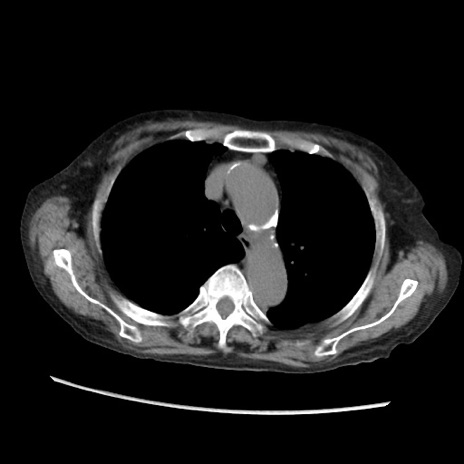

症例31(横断像)

【症例】80歳代 女性

【主訴】腹部膨満感

【現病歴】他院にて肝硬変にてフォロー中。1週間前から便秘、腹部膨満感、臍部腫瘤あり受診となる。

【既往歴】肝硬変

【身体所見】腹部膨隆あり、皮膚変化なし、疼痛なし。

【データ】WBC 4600、CRP 0.25